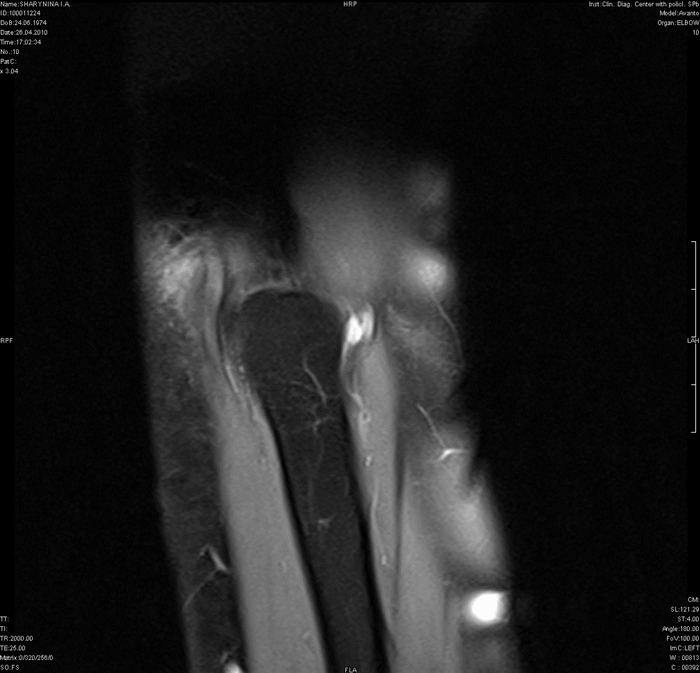

МРТ локтевого сустава

Травма в области локтевого сустава чаще, чем в других местах, осложняется нарушением кровообращения, при котором руку может спасти только раннее оперативное вмешательство. Диагностика заболеваний локтевого сустава обычно не вызывает затруднений, поскольку он хорошо доступен для обследования. Среди всех поражений локтевого сустава чаще всего встречаются травматические повреждения (особенно у спортсменов). Переломы костей, образующих локтевой сустав, хорошо диагностируются при рутинном рентгенологическом исследовании. Применение МРТ необходимо для визуализации повреждений суставной капсулы, связок и сумок локтевого сустава. Разрывы локтевой боковой связки представляют собой один из наиболее характерных видов спортивных травм и часто сочетаются с разрывами капсулы сустава, переломами внутреннего надмыщелка и венечного отростка локтевой кости. Прямыми МРТ признаками разрыва локтевой боковой связки являются прерывистость хода ее волокон, наличие жидкости в полости сустава и отек мягких тканей вокруг. Часто, как следствие острой или хронической травмы, развивается бурсит в области локтевого отростка с наличием выпота в поверхностной сумке, который отчетливо виден при осмотре пациента. Другим характерным повреждением локтевого сустава является эпикондилит - хроническое дегенеративно-дистрофическое заболевание, обусловленное постоянной травматизацией сустава у спортсменов (теннисистов, бейсболистов, игроков в гольф, боулинг и др.), а также у людей определенных профессий (каменщиков, маляров, швей и др.). На МРТ изображениях определяется утолщение или истончение сухожилий мышц, прикрепляющихся к надмыщелкам плечевой кости, частичные разрывы этих связок с выпотом и отеком вокруг.

Посттравматическая энтезопатия общего сухожилия мышц-разгибателей («латеральный эпикондилит»)